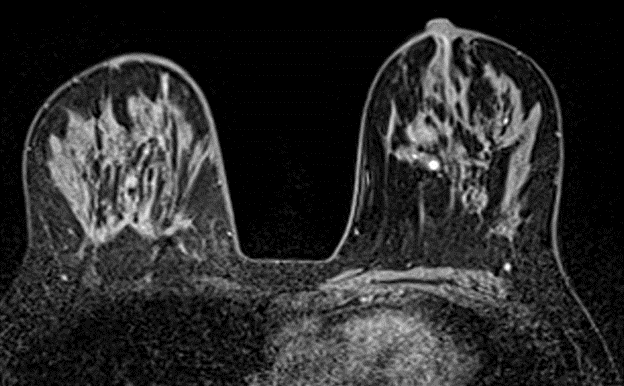

The Breast Imaging section of Diagnostic Radiology offers a full range of services. Breast imaging services include 3D screening and diagnostic mammography, breast ultrasound, magnetic resonance imaging (MRI), and interventional procedures. The multidisciplinary breast center is located on the 9th floor of the Center for Health and Healing 2.

Fellows spend the year in the OHSU breast imaging center, receiving clinical training in digital breast tomosynthesis, breast ultrasound, breast MRI, and all associated interventional techniques including aspiration, steroid injection, biopsy, and preoperative localization.  The weekly schedule includes time on diagnostics, screenings, interventions, MRI, interpretation of outside imaging, and academic time.